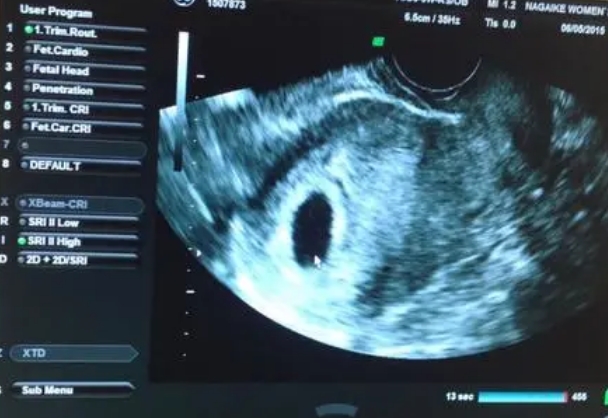

怀孕初期,许多准妈妈会面临是否需要做阴超检查的困惑。阴超(阴道超声)作为一种常见的产前诊断手段,能早期发现宫外孕、胎停育等问题,但不少孕妇担心这种检查会影响胚胎发育。事实上,阴超的安全性已得到广泛验证,其声波能量远低于可能致畸的阈值,且无电离辐射风险。本文将从医学原理、临床研究及注意事项等方面,详细解答这一疑虑。作为妇产科医生,每天都要解答这类疑问。先说结论:正规操作的阴超检查不会伤害胚胎,我们从

怀孕初期做阴超比b超更能准确诊断怀孕情况。由于阴道超声探头与子宫的近距离,其能够生成更高分辨率的图像,特别是在早期妊娠阶段,怀孕时间短,胚胎体积也比较较小且结构未完全发育时,这种时候阴超的高清晰度成像的重要性尤为显著。阴道超声是通过将超声探头插入阴道内部,接近子宫和附件区域进行的检查,而腹部超声则是将探头置于腹部皮肤表面进行检查,怀孕初期建议阴超检查则是因为它有更高的图像清晰度、可以更早检测出怀孕

阴超是更常见和推荐的方式。因为阴超的图像质量更高,能够更清晰地观察到胚胎的早期发育情况。阴超是将超声探头放入阴道内进行检查的方法。而腹部B超则是通过腹部皮肤进行的检查。因此,在试管胚胎移植后的早期,医生通常会采用阴超的方式进行检查,当然,每个人的情况不同,最终的选择应该根据医生的建议而定。试管胚胎移植(IVF)是一种辅助生殖技术,帮助许多不孕不育的夫妇实现生育梦想。在试管胚胎移植后,医生会安排一系